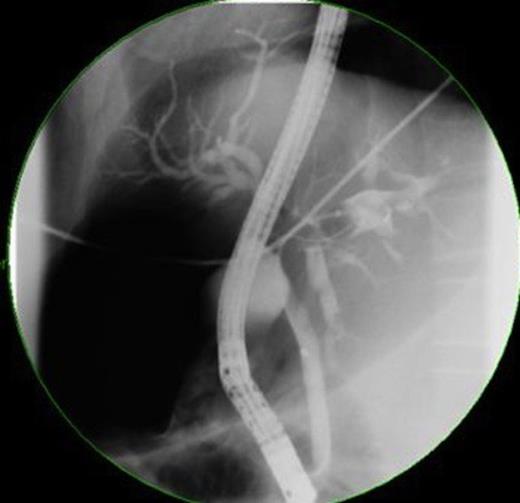

ERCP showed casts occupying the hepatic ducts and motile liver flukes were identified. A 10-French stent was inserted and sphincterotomy performed to drain sludge. ERCP histopathology specimens revealed necrotic tissue with eosinophils, although no ova/parasites were visualised. Stool samples did not identify ova so blood samples were taken for serology testing including Clonorchiasis andOpisthorchiasis (results pending at time of publication). Total quantitative immunoglobulins revealed elevated IgA (7.05g/L) and total IgE (874 IU/ml), consistent with a parasitic infection and/or neoplasia. The patient was given 3 doses of 75mg/kg praziquantel for parasites; ciprofloxacin and metronidazole for cholangitis and initiated on warfarin for portal vein thrombosis. Three weeks later his symptoms resolved and stent was removed, ERCP indicating drainage and dead flukes. Despite radiological findings suggesting neoplasia, possibility of liver abscess was still likely. A decision was made not to perform liver biopsy, due to potential for peritoneal tumour seeding if the mass was neoplastic and instead he was monitored on an outpatient basis.

Over the next few months, the man was admitted for repeated cholangitis episodes. ERCP now indicated intra-hepatic duct filling defects (figure 4) and sediment was removed with new stents placed. Repeat abdominal-CT scans indicated the mass was similar in size. Following these presentations, the multidisciplinary team decided to undertake laparoscopic liver biopsy.